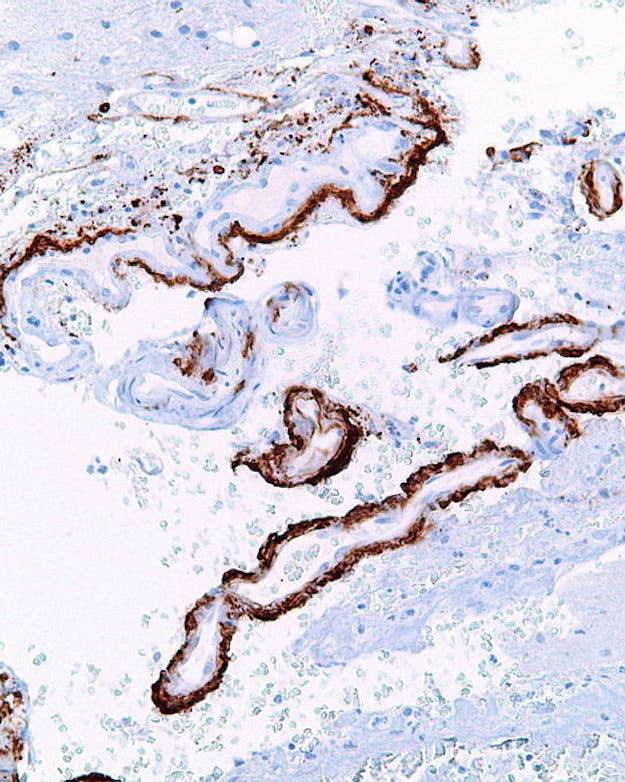

Sterk vergrote foto van hersencellen met samengeklonterde slierten van bèta-amyloïde, het eiwit verantwoordelijk voor alzheimer.

Wikimedia Commons, Nephron via CC BY-SA 3.0Meer of minder bescherming